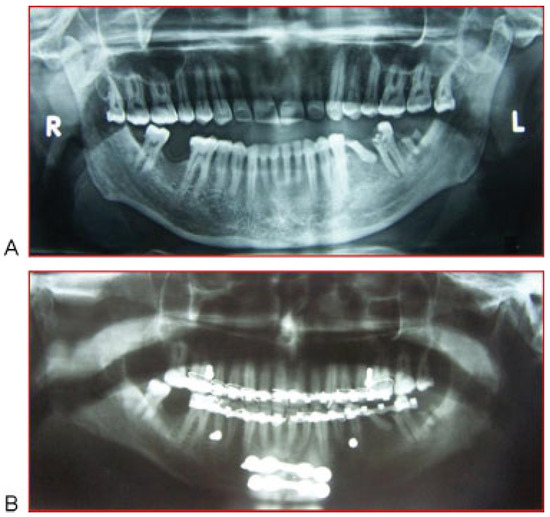

:Case Report 1